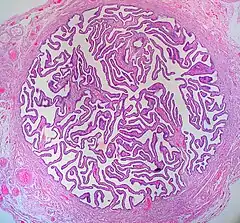

Histología

La pared de las trompas en su cara interna (luminal) es compleja. La mucosa está dispuesta sobre pliegues longitudinales denominados "plicas".

La estructura histológica varía en los diferentes segmentos, lo que permite una funcionalidad adaptada en cada uno. Se observan tres capas tisulares diferentes mucosa (endosalpinge), muscular (miosalpinge) y serosa, sus proporciones varían en los distintos segmentos.[12][13]

Internamente, cada oviducto está cubierto de una mucosa con pliegues ("plicas"), con un epitelio cilíndrico pseudoestratificado con células ciliadas, células caliciformes y células no ciliadas intercalares (o peg). Las células epiteliales descansan sobre una lámina basal y una lámina propia conjuntiva laxa subyacente.

La capa media contiene músculo liso, donde se puede distinguir una capa circular interna y otra longitudinal externa.

La capa más externa consiste en la serosa de epitelio simple plano, con tejido conectivo subyacente donde se pueden observar grandes vasos sanguíneos y nervios.